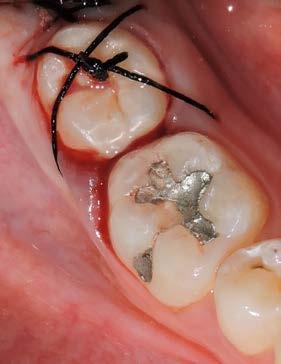

44 | CASO CLÍNICO

Autotrasplante de terceros molares mediante el uso de una guía de impresión tridimensional: Revisión de la literatura y reporte de un caso clínico